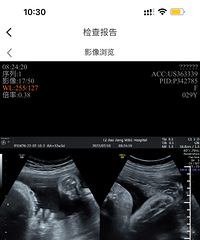

预产期:2023年5月20日建卡医院:温岭市妇幼保健院产检医院:温岭市妇幼保健院胎宝宝小名:还没取呢生产医院:未定哦B超照片/孕期相关照片一张